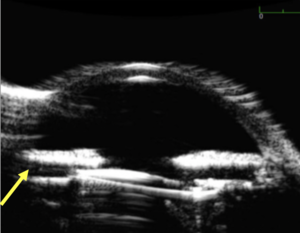

UGH syndrome is classically associated with the triad of chronic inflammation, recurrent bleeding and iris transillumination defects. Elevated intraocular pressure (IOP) is noted with advancing dysfunction of the trabecular meshwork (TM) and is occasionally associated with iris neovascularization and cystoid macular edema. The patient may present with complaints of episodic blurring of vision (repeated hyphemas) photophobia, red eye and pain. Ultrasound biomicroscopy (UBM) is helpful to determine position of the IOL since the points of interest (haptic-iris-sulcus relationship) are often not visible on slit lamp exam (Figure 2). It is important to note that UBM can often indicate apposition of the haptic and/or optic against specific ocular structures (like the iris) but is not definitive evidence that the lens is outside of the capsular bag (since capsular bag stability may be compromised and allowing for tilting and contact with adjacent structures). Gonioscopy is essential to determine presence of blood that may not be visible without direct view of the angle. The level of angle pigmentation (look for distribution of pigment in all quadrants and examine meticulously for any possible tumors that may mimic UGH syndrome) should also be noted (Figure 3). Gonioscopy can also identify points of contact between the haptics and the iris which appear as anterior outpouchings of iris tissue. Gonioscopy is also key to identify any neovascularization of the iris or angle, which can be a feature of chronic UGH syndrome but may also indicate presence of neovascular glaucoma from ischemic processes (which can mimic UGH syndrome) unrelated to IOL position. Elevation of IOP can occur due to all factors noted above with both physical plugging of the TM (from pigment, blood and inflammatory cells) as well as direct mechanical destruction of the TM from compression and/or rubbing against IOL structures.